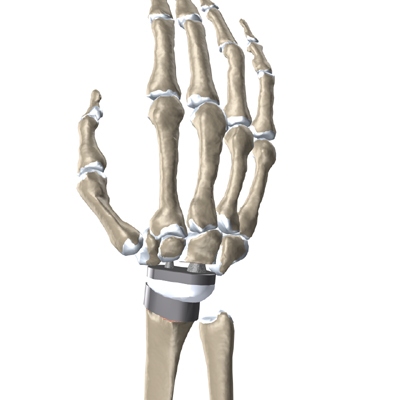

If both wrists require surgery, many surgeons recommend fusing one wrist for strength and replacing the other wrist with an artificial wrist joint. This allows the patient to have one strong hand and one hand with a good range of motion.

The major reason that artificial joints eventually fail is that they loosen where the metal or cement meets the bone. A loose joint prosthesis causes pain. Once the pain becomes unbearable, another operation will probably be needed to fix the artificial joint or to perform a wrist fusion.

There have been many advances in extending the life of artificial joints. However, most replacements will eventually loosen and require another surgery. In the case of an artificial knee, you can expect about 12 to 15 years, but artificial wrist joints tend to loosen sooner. The risk of loosening is much higher in younger, more active patients.